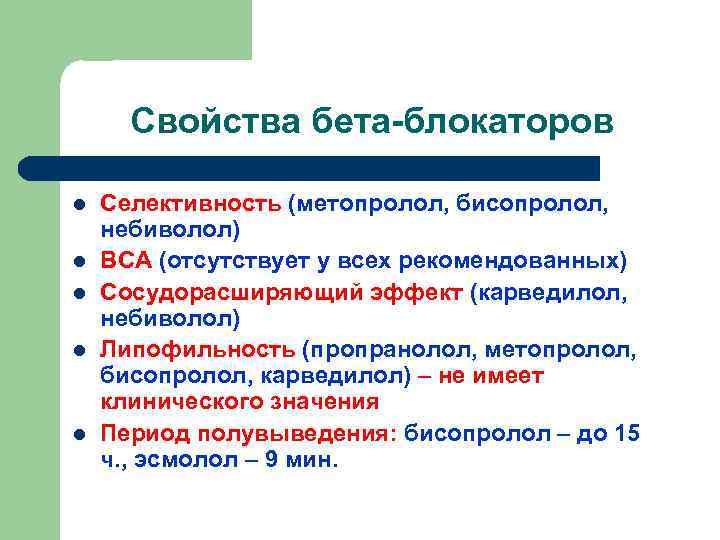

Свойства бета-блокаторов l l l Селективность (метопролол, бисопролол, небиволол) ВСА (отсутствует у всех рекомендованных) Сосудорасширяющий эффект (карведилол, небиволол) Липофильность (пропранолол, метопролол, бисопролол, карведилол) – не имеет клинического значения Период полувыведения: бисопролол – до 15 ч. , эсмолол – 9 мин.

Клинические эффекты бетаблокаторов l l Антиишемический Антигипертензивный Антиаритмический Положительный инотропный

Клинические эффекты бетаблокаторов l l Эффект бета-блокаторов тем больше, чем выше исходные тонус СНС и ЧСС Оптимум эффекта при достижении ЧСС целевого уровня: 55 -60 в мин 50 и менее (при отсутствии блокады)

Внимание: небиволол (небилет) l l Эндотелиальная дисфункция – триггер и медиатор повреждения эндотелия и последующего атеротромбоза коронарных артерий. Небилет – бета-блокатор, уменьшающий эндотелиальную дисфункцию. Небилет заменяет два антиишемических препарата: бета-блокатор и нитрат. Небилет оптимален при сочетании ИБС и АГ.

Характеристика некоторых бетаблокаторов Препарат Селект-ть ВСА Другие названия Дозировка (мг) Пропранолол нет Обзидан, анаприлин 20 -80 х 4/сут Метопролол Бета-1 нет Беталок-ЗОК, эгилок, корвитол 50 -200 х 2/сут Бисопролол Бета-1 нет Конкор, бисогамма 10/сут Надолол нет Коргард 40 -80/сут Пиндолол нет есть Вискен 2, 5 -7, 5 х 3/сут Небиволол Бета-1 нет Небилет 2, 5 -5/сут Карведилол Бета-1 нет Дилатренд, акридилол 25 -50 х 2/сут